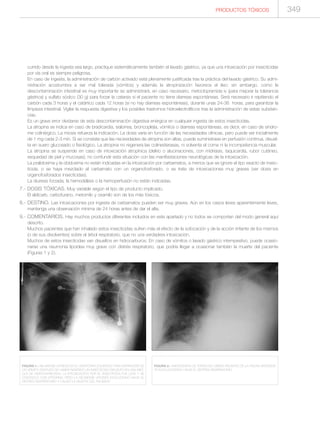

FIGURA 1.- RADIOGRAFÍA DE TÓRAX DE UNA PA-

CIENTE CON UNA INTOXICACIÓN MEDICAMENTOSA

AGUDA. SE HA COLOCADO UNA SONDA POR VÍA

NASAL PARA REALIZAR UN LAVADO GÁSTRICO,

PERO LA MISMA SE HA UBICADO EN EL BRONQUIO

PRINCIPAL DERECHO (FLECHAS).

yatrogenia por colocación inadecuada de una sonda para el lava-

do gástrico (Figura 1). También es frecuente que la vía aérea se

obstruya por tapones de moco cuando coexiste el coma y la

ingesta de fármacos anticolinérgicos (Figura 2).